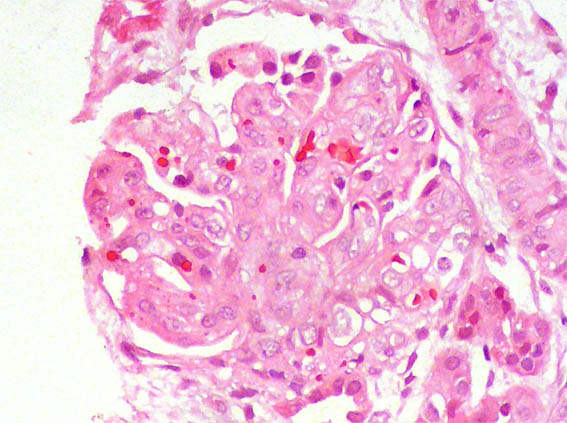

Se hace biopsia renal. Observe las imágenes.

Figura 2. H&E, X400.